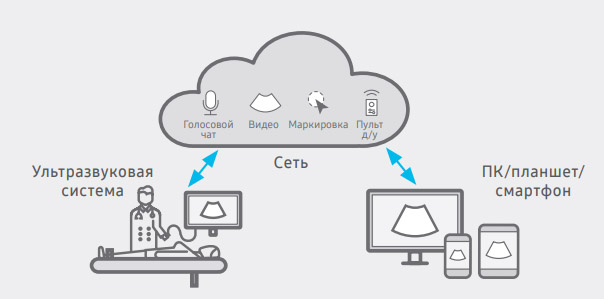

Обмен изображениями, обсуждение результатов и дистанционное управление ультразвуковой системой в реальном времени

SonoSync™ — приложение, которое предназначено для обмена изображениями между лечащими врачами и врачами ультразвуковой диагностики, позволяющее им обсудить лечебный план пациента или провести обучение. Оно используется на ПК, смартфонах и других мобильных устройствах. В приложение включены функции голосового чата, текстового чата и маркировки в реальном времени, которые облегчают обмен информацией. Также предусмотрена функция MultiVue, с помощью которой можно просматривать несколько ультразвуковых изображений на одном экране.